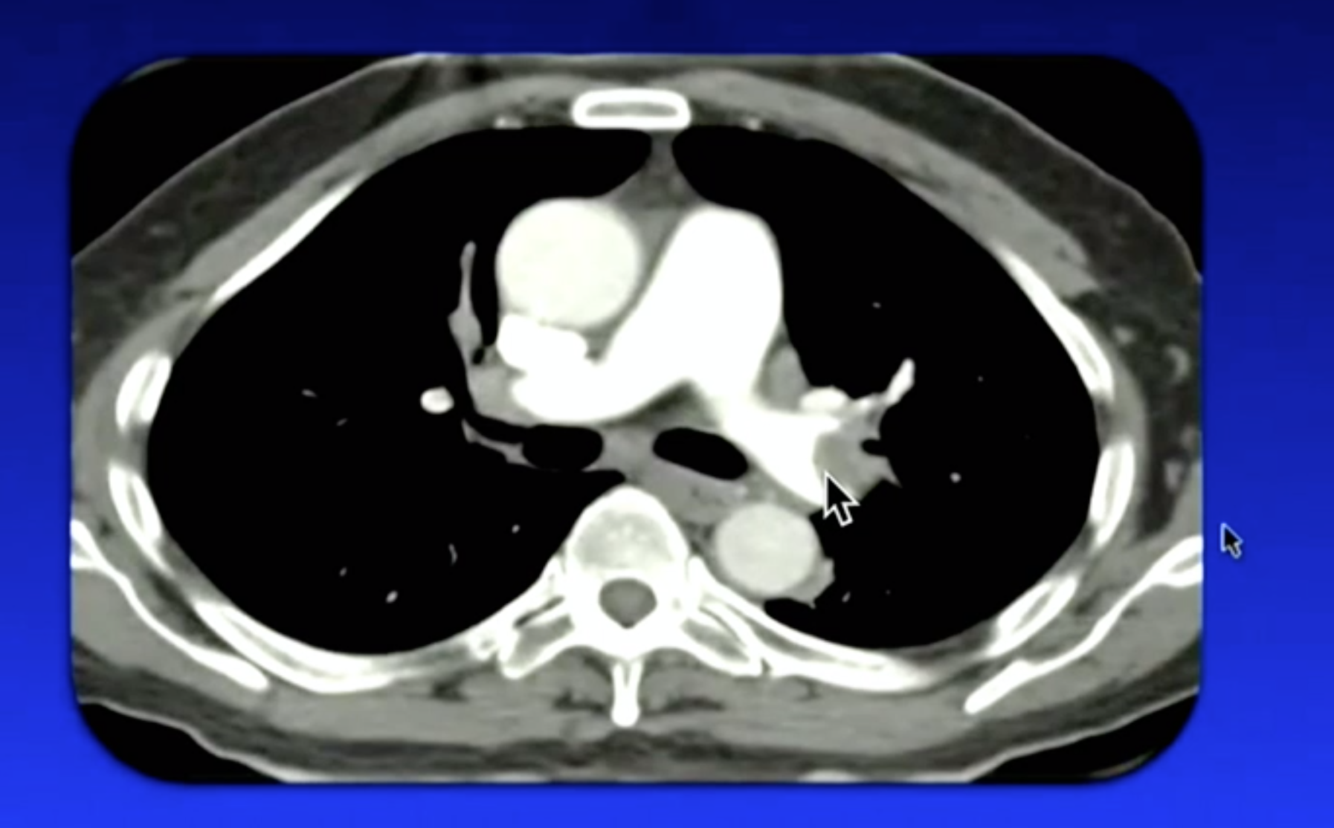

What is shown here?

Saddle Embolism: When it goes over bifurcation of pulmonary artery

eccentric clot